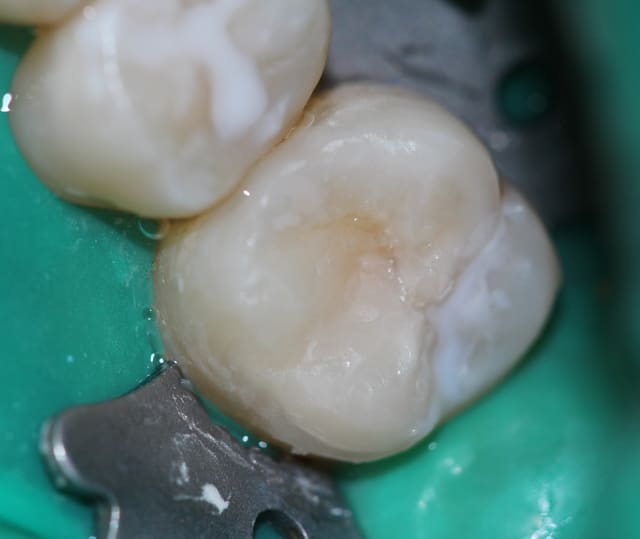

P1020718_nq7p7t.jpg

Voir le message contenant cette image